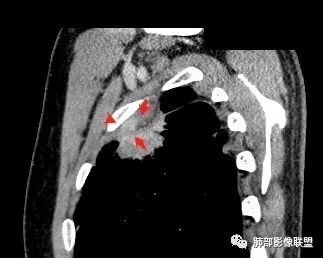

如下图病例红色箭头的是典型栽赃:

南边 :

而该病例栽赃不明显,与增厚的胸膜分界比较清晰

下面这个病例这也是栽赃